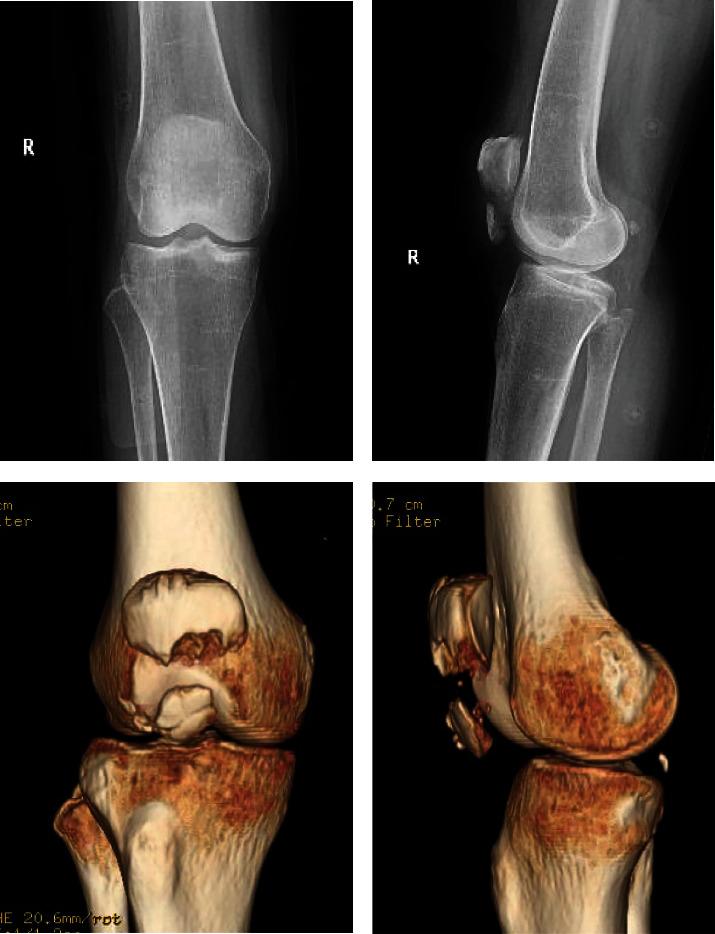

缝合锚与双滑索技术治疗髌下骨折的临床效果。

Clinical Effect of Suture Anchor and Double-Pulley Technique in the Treatment of Inferior Patellar Fracture.

To evaluate the efficacy of suture anchor combined with double-pulley technique for subpatellar comminuted fractures compared with wire vertical suture and Krachow in the treatment of subpatellar fractures.

Retrospectively selected 48 patients with subpatellar pole comminuted fracture admitted in our hospital from February 2013 to July 2019, 25 patients with double-pulley technique (group A), and 23 patients with vertical wire suture with Krachow suture. Patient age, gender, AT/OTA typing, injury mechanism, follow-up time, surgical time, bleeding volume, mean fracture healing time, and postoperative complications were recorded. The Insall-Salvati index immediately and 6 weeks after surgery. Bostman scores and knee activity were recorded at each follow-up, and month 12 was taken as the final result.

Time of surgery in group A (46.52 min) was significantly shorter than in group B (76.30 min). Intraoperative bleeding in group 15.1 ml, B, group 15.9 ml. Both incisions healed in stage I, averaging clinical healing of patella fracture within 10 weeks. There was no significant difference in mean Bostman score and knee activity at month 12 (group A: 28.4, 124.8°; group B: 28.1, 125.7°). There was no significant statistical difference in the Insall-Salvati index immediately or 6 weeks between the two groups. Group B patients had two wire fractures, fracture healing and the wire removed one year after surgery, and the remaining patients had no complications such as internal fixation loosening, fracture, delayed healing, or nonhealing of fracture.

Compared with the treatment of subpatellar fracture with wire vertical suture and Krachow method, suture anchor with double-pulley technique has short operation time, reliable fixation, and less complications. Patients can have early functional exercise and good knee function recovery without secondary surgery. It can be considered as an alternative therapy for this fracture and deserves clinical adoption and promotion.